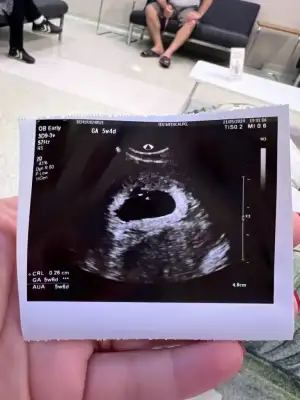

Ekledim canım , hoş geldin aramızacinnabon canım beni de tabloya ekleyebilirsin. bugün keseyi gördük. yaş 36. ilk bebek. 16 nisan SAT. kese 5+0. tahminim kız. istanbul. tahmini doğum tarihi 19 ocak 2025

ortada görülen beyaz küçük nokta bebişmiş kenardaki beyazda yolk sac dedikleri şey. 0.26 cm miş